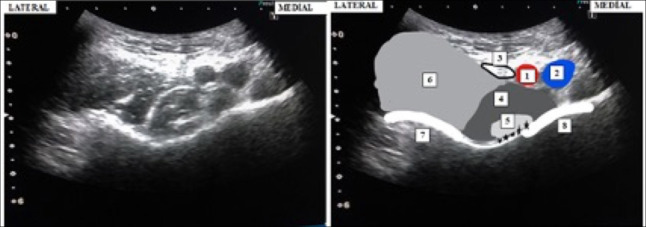

Methods: Patients who underwent surgery for intertrochanteric femoral fractures between June 2021 and June 2024 were retrospectively analyzed. The study included patients who underwent surgery for intertrochanteric femoral fractures using a proximal femoral nail under spinal anesthesia, combined with either a PENG block or an S-FICB. The patients were divided into two groups: those who underwent a PENG block were assigned to Group I, and those who received an S-FICB were assigned to Group II. Functional assessments included perioperative numerical rating scale (NRS) scores, the timing and amount of systemic analgesics use, patient satisfaction, nausea, vomiting, and motor muscle strength.

Results: The spinal positioning score was significantly better in Group I (p<0.01). NRS scores were significantly lower in Group I at the 6th and 12th hours during exercise (p<0.001). Patient satisfaction scores were also significantly higher in Group I (p=0.04). The time to first opioid use was earlier, and the total opioid dose was higher, in Group II (p=0.03 and p=0.04, respectively).

Conclusion: The PENG block, with its more potent analgesic effect, easier positioning, lower opioid consumption, and higher patient satisfaction, emerges as a promising option for hip fracture surgery.